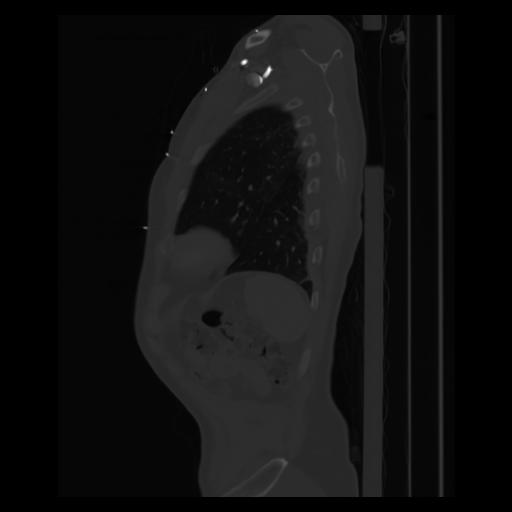

30 CUERPO,CE,Sagittal,3.000,CUERPO,Sagittal,